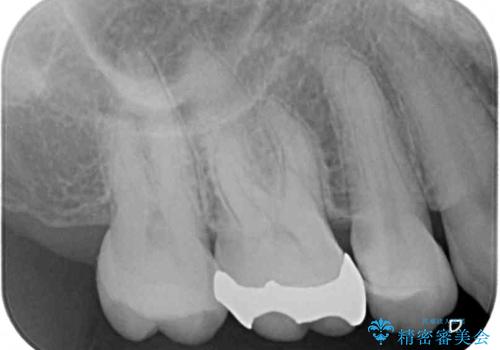

診査の結果、不適合な銀歯の隙間からむし歯が進行しており、更には頬側、口蓋側ともに歯肉縁付近に強い知覚過敏症状が認められました。

健全歯質が多いため、インレーおよびむし歯を除去した上で知覚過敏を緩和させる処置を行うことが望ましいと判断されましたが、知覚過敏の症状が一向に改善されないため、全体をセラミッククラウンで補綴することとしました。